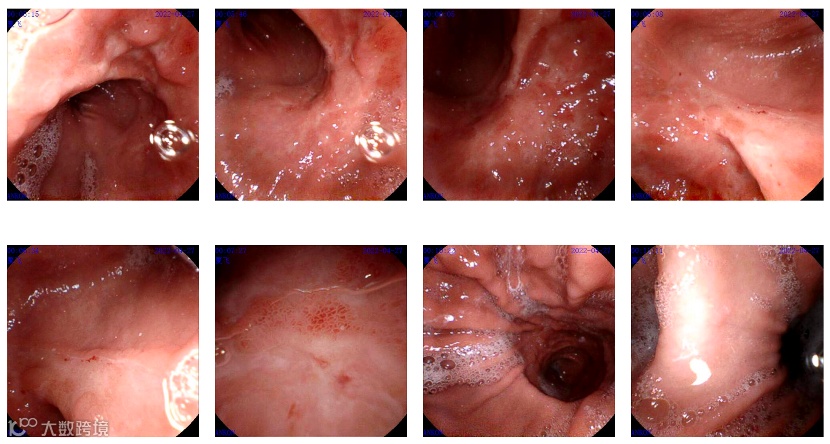

检查结果令人意外。磁控胶囊胃镜报告显示:菲姐的胃部有花斑样充血,胃体下段粘膜粗糙,可见类溃疡样改变,周围粘膜聚集,局部变形。这与此前怀疑的胃食管反流症状不完全吻合,预示着病情可能没有预想的这么简单。

图:磁控胶囊胃镜检查报告(部分)

接下来,菲姐做了进一步的电子胃镜检查和活检病理。在进一步的检查中,医生在她的胃角处发现了白斑凹陷,病理结果对菲姐来说是一个巨大的打击——她被诊断为低分化腺癌,部分呈印戒细胞癌。

图:电子胃镜报告(部分)